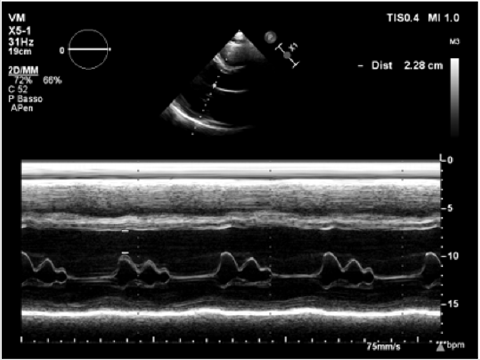

Physical examination showed a muscular man, the apex beat was not evident, the jugular at baseline showed an absent X’ descent with a positive hepato-jugular reflux and heart sounds were regular at the auscultation ; there was also minimal ankle swelling and , bilateral basal crackling rattles were audible at lung auscultation. The ECG showed a sinus rhythm with a frequency of 88 bpm, signs of left atrial enlargement, a left axial deviation and negative T-waves on D1 and aVL and from V4 to V6; no previous recent ECG was available for comparison. Chest X-ray showed pulmonary edema and an acute bronchopneumonia focus. Transthoracic echocardiography (TTE) revealed a dilated cardiomyopathy with severe left ventricular systolic dysfunction (LVEF 23% calculated with the Simpson biplane method) and dilatation (telediastolic diameter 79 mm) with moderate uniform hypertrophy (Figure 1a & 1b). There was grade II diastolic dysfunction (E/A waves ratio 1,9; E wave deceleration time 144 msec), “B-bump” on M-mode examination at the mitral valve level and an average E/e’ at tissue doppler analysis at the upper limit of the “grey zone”: 14 (Figure 2a-2d); global longitudinal peak systolic strain (GLPSS) was -7,4%; the left atrium was dilated; the right ventricle was dilated, slightly hypocontractile (tricuspidal annular plane systolic excursion, TAPSE, 16 mm) with a dilated right atrium; the inferior cava vein showed a normal dimension and collapsibility.